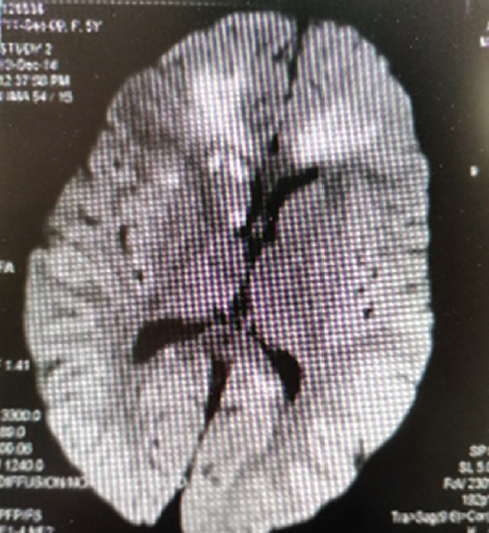

Проведение DWI МРТ у 63 % детей показало наличие множественных двусторонних очагов инфарктов, вероятнее всего развившихся вследствие васкулита мелких сосудов (рис. 2).

Рис. 2. Магнитно-резонансная томограмма головного мозга ребенка, 2 года 4 мес. На DWI множественные инфаркты мозолистого тела и правого хвостатого ядра / Fig. 2. MRI of a child, 2,4 years old. The DWI shows multiple infarctions of the corpus callosum and the right caudate nucleus